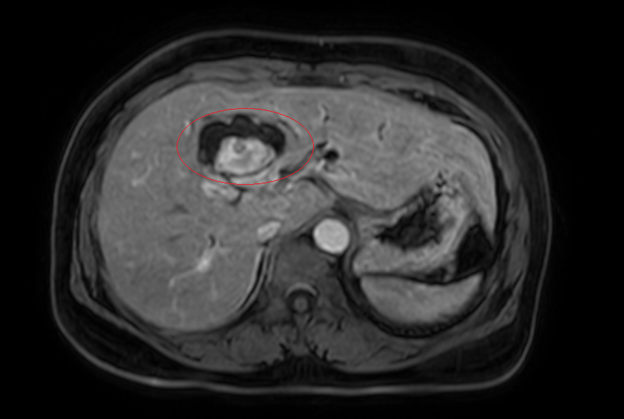

Hình ảnh giãn khu trú đường mật gan trái, tạo cấu trúc dạng nang và sỏi đường mật bên trong (vòng tròn đỏ), chèn ép kèm giãn đường mật trong gan hai bên trên phim chụp MRI - Ảnh BVCC

Bệnh nhân nữ, 59 tuổi, nhập viện trong tình trạng vàng da, ngứa và đau vùng hạ sườn phải kéo dài. Kết quả chẩn đoán hình ảnh cho thấy tổn thương đường mật trong gan kèm sỏi và giãn đường mật.

Sau hội chẩn đa chuyên khoa, các bác sĩ xác định bệnh nhân mắc đồng thời hai ung thư nguyên phát, thay vì một khối u di căn.

Cụ thể: Ung thư đại tràng phải: Giai đoạn sớm (IA), chưa di căn hạch; Ung thư đường mật trong gan: Giai đoạn tiến triển (IIIB), có xâm lấn và di căn hạch.

Đáng chú ý, ung thư đường mật trong gan thường có tiên lượng xấu do phát hiện muộn. Tuy nhiên, ở bệnh nhân này, bệnh được phát hiện tương đối sớm nhờ triệu chứng tắc mật, tạo điều kiện để can thiệp phẫu thuật triệt căn.